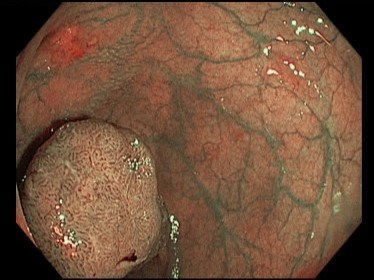

Kết quả nội soi lần hai ghi nhận đại tràng trái có một tổn thương dạng polyp nghi ngờ ác tính. Kết quả sinh thiết sau đó là carcinôm tuyến grad 2.

mac 2 loai ung thu anh 1

Khối u ở đại tràng trái người bệnh. Ảnh: BVCC.